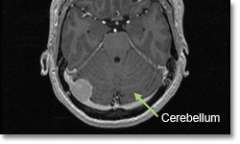

Meningioma Pfossa

Location - Posterior Fossa (area where the cerebellum is)

Common Symptoms

- Unsteadiness and incoordination, hydrocephalus (increased pressure inside the brain), voice and swallowing difficulties.